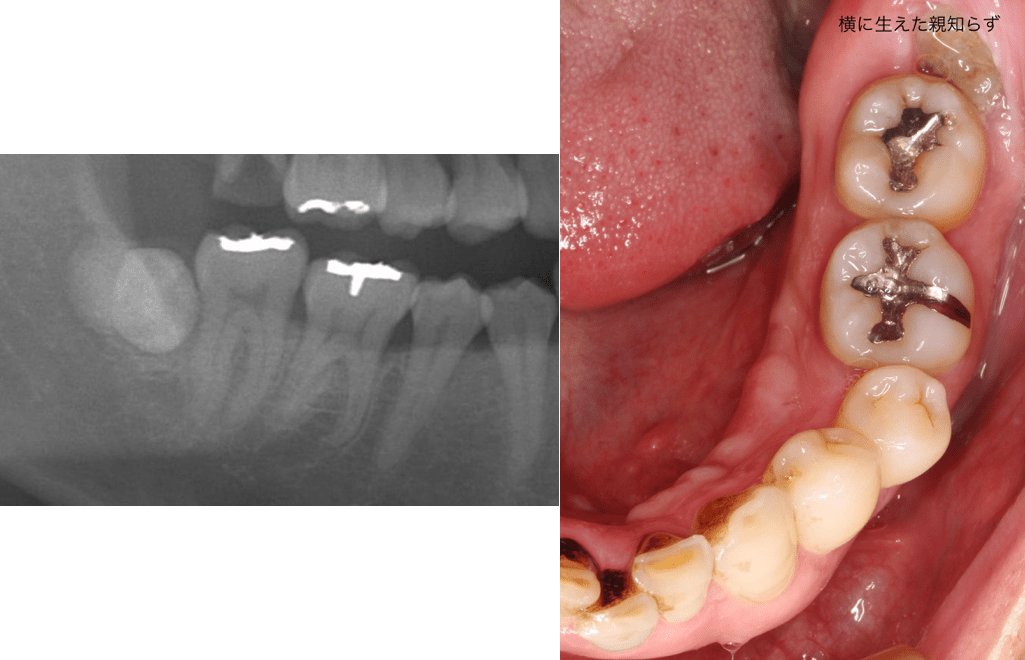

親知らず 少し 見える. 親知らずを抜歯しました。 歯医者さんは抜くのにとても苦戦されたみたいで 歯茎を切開してあごの骨を少し削ったり ノミのようなもを使用したり 最終的に親知らずを二つに割ることで抜けました。 トータルで1時間半~2時間近かったと記憶しています。 少しだけ頭が見えていたので歯茎も切らず骨も削らず抜きました! 所要時間麻酔等含めて 約15分 ! 抜歯後にレントゲンを再度とりました、、、 親知らずの横の歯の部分に黒い影が、、、 とりあえず3dct撮影をしましょう。 とのことで、撮った画像がこちら.

少しだけ頭が見えていたので歯茎も切らず骨も削らず抜きました! 所要時間麻酔等含めて 約15分 ! 抜歯後にレントゲンを再度とりました、、、 親知らずの横の歯の部分に黒い影が、、、 とりあえず3dct撮影をしましょう。 とのことで、撮った画像がこちら. こんにちは! いしはた歯科クリニック院長の石幡一樹です。 今日の久喜は午前中からゲリラ雨で外は湿度が非常に高いです( *´艸`) 歯の話ですが今回は難しい親知らずの抜歯についてです。 参考:過去のご相談 ※親知らず抜歯のための口腔外科選び、大学病院か個人の診療所か 他 お世話になります。 先生方よりご回答いただき、一部だけ歯茎から見えている親知らずの抜歯をしようと決めたのですが、かかっている歯科の再診では抜歯しなくてもよいと言われ、再び迷っている.

少しだけ頭が見えていたので歯茎も切らず骨も削らず抜きました! 所要時間麻酔等含めて 約15分 ! 抜歯後にレントゲンを再度とりました、、、 親知らずの横の歯の部分に黒い影が、、、 とりあえず3Dct撮影をしましょう。 とのことで、撮った画像がこちら.